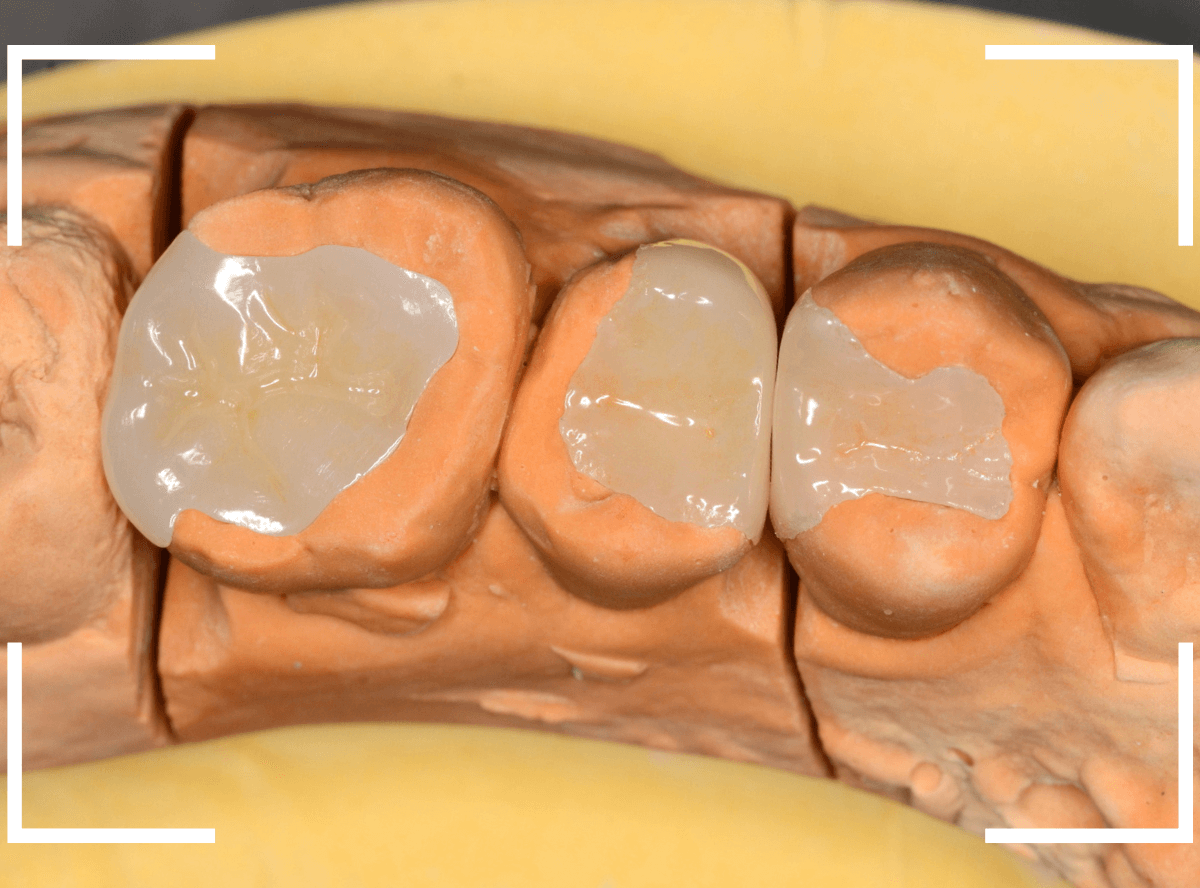

Case.26 4歯連続したセラミック・インレー

4本連続して歯と歯の間の虫歯を治療した患者さんのケースです。

虫歯を再発させないためには、歯と歯のすき間を物がつまらないよう、精密に再製する必要があります。

患者さんのご希望により、セラミック・インレーで修復する事になりました。

模型上で歯と歯のすき間を精密に再現・調整できるのが、セラミック・インレーの大きな利点です。

歯をトリミングして、型を取ります。

模型上で精密に製作します。

最終setした状態です。

左側の大臼歯2本が、ジルコニア・インレー

右側の小臼歯2本が、E-MAX・インレー

になります。

見た目にほとんど遜色ない仕上がりにできました。

普段あまりしない、4歯連続のインレー治療でしたが、精密に仕上げ・setする事が出来てホッとしました。